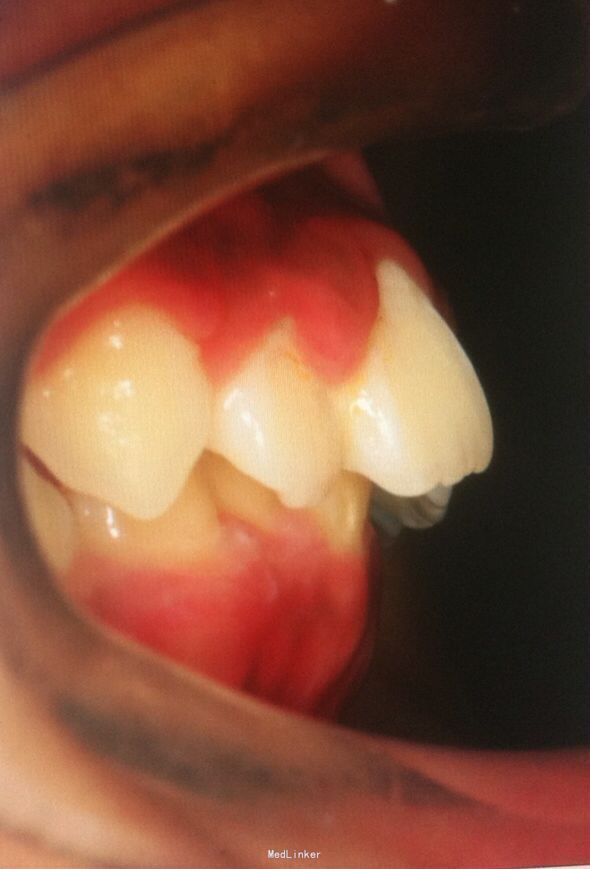

恒牙期 25正锁合 磨牙中性关系 前牙一度深覆盖深覆合 牙列拥挤 张口型异常

安氏一类 不拔牙矫治,直丝弓矫治器,排齐整平上下牙列,治疗后前牙覆合覆盖正常,磨牙中性关系,维持现有面型